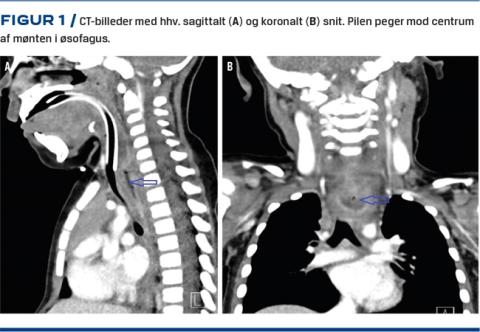

Pga. klinisk forværring blev hun tre måneder senere henvist til bronkoskopi. Her fandt man trachea komprimeret, og man foretog derfor i samme seance fleksibel og rigid øsofagoskopi, der afslørede en 2 cm stor, blå plastmønt, der var indgroet i den proksimale øsofagus. En akut CT viste normale anatomiske forhold fraset mønten (Figur 1), der herefter blev fjernet ved rigid øsofagoskopi uden perforation af øsofagus.